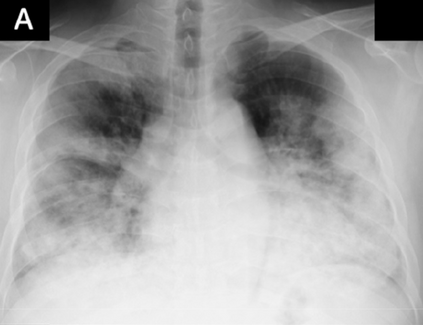

Across the world's coronavirus disease 2019 (COVID-19) hot spots, the need to streamline patient diagnosis and management has become more pressing than ever. As one of the main imaging tools, chest X-rays (CXRs) are common, fast, non-invasive, relatively cheap, and potentially bedside to monitor the progression of the disease. This paper describes the first public COVID-19 image data collection as well as a preliminary exploration of possible use cases for the data. This dataset currently contains hundreds of frontal view X-rays and is the largest public resource for COVID-19 image and prognostic data, making it a necessary resource to develop and evaluate tools to aid in the treatment of COVID-19. It was manually aggregated from publication figures as well as various web based repositories into a machine learning (ML) friendly format with accompanying dataloader code. We collected frontal and lateral view imagery and metadata such as the time since first symptoms, intensive care unit (ICU) status, survival status, intubation status, or hospital location. We present multiple possible use cases for the data such as predicting the need for the ICU, predicting patient survival, and understanding a patient's trajectory during treatment. Data can be accessed here: https://github.com/ieee8023/covid-chestxray-dataset